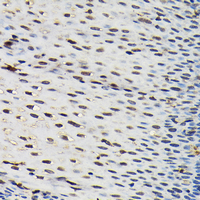

Immunohistochemical analysis of SFPQ staining in human esophageal formalin fixed paraffin embedded tissue section. The section was pre-treated using heat mediated antigen retrieval with sodium citrate buffer (pH 6.0). The section was then incubated with the antibody at room temperature and detected using an HRP conjugated compact polymer system. DAB was used as the chromogen. The section was then counterstained with haematoxylin and mounted with DPX. -